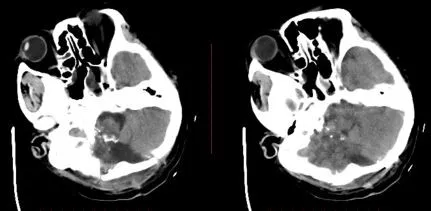

术后CT

术后呼吸机支持治疗3周后脱机,GCS 15,双侧肢体自主活动,出院康复。